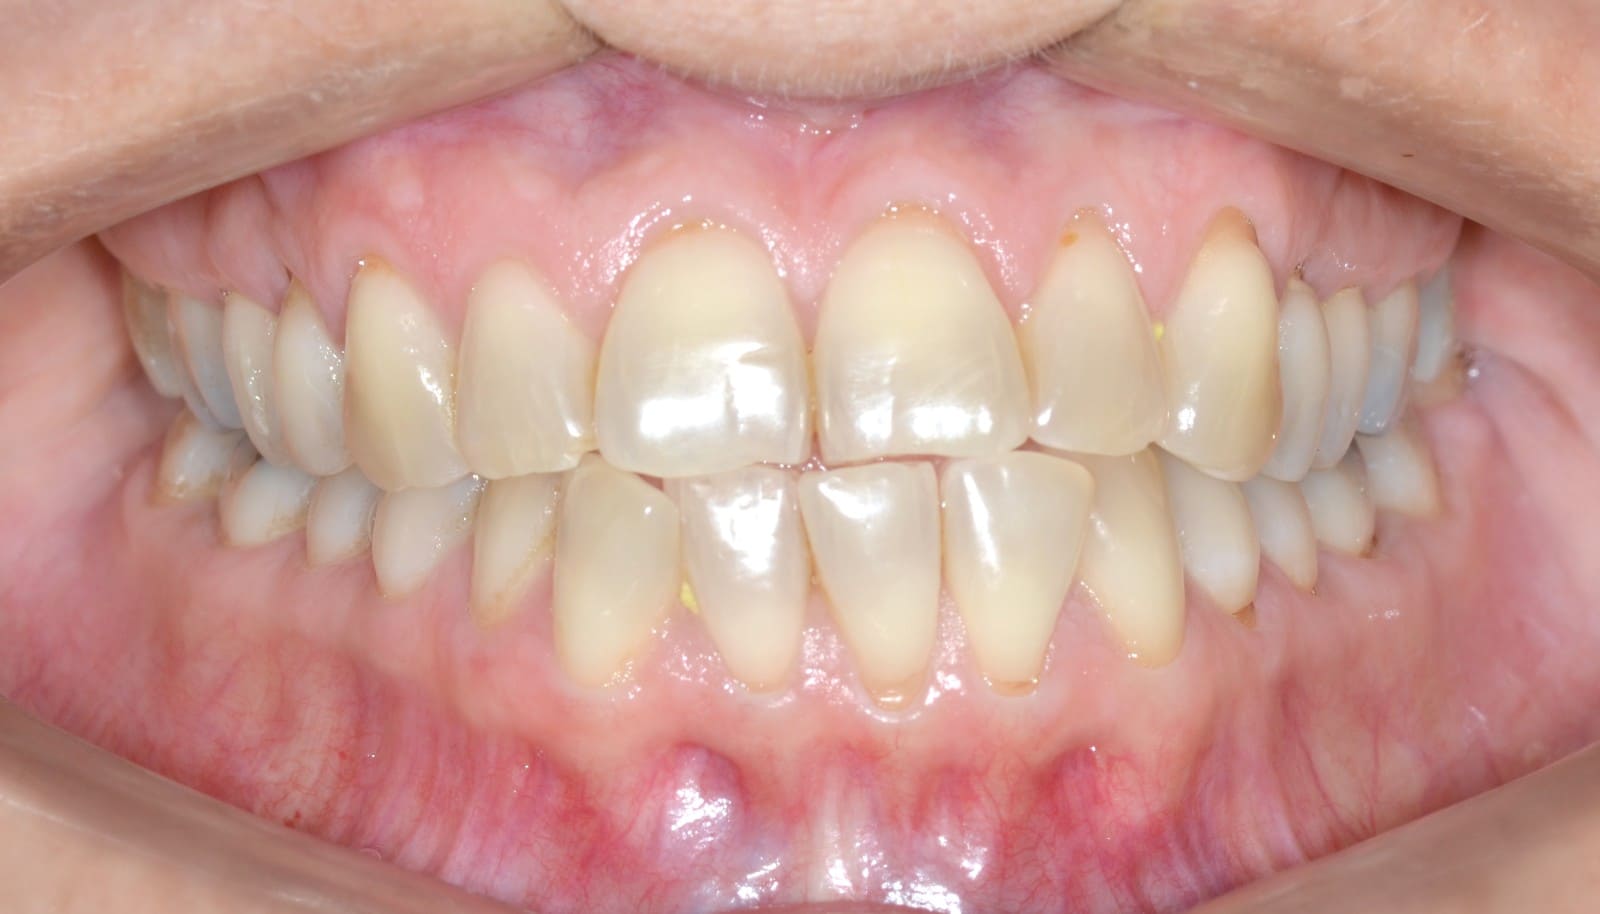

Initial

Final

Invisalign Comprehensive Conditions – Anterior crossbite – Class III – Crowding – Mandibular midline deviation – Rotations

Clinical Indications

- Anterior crossbite

- Class III

- Crowding

- Mandibular midline deviation

- Rotations